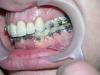

ZuzaZuza Опубликовано 25 мая, 2009 Автор Поделиться Опубликовано 25 мая, 2009 Фото Ссылка на комментарий

Orthodoc Опубликовано 25 мая, 2009 Поделиться Опубликовано 25 мая, 2009 ФотоЗубная дуга не может расшириться, если стоят сегментные дуги, т. к нет опоры. Если у Вас стоят единичные коронки во фронтальном участке, то необходимо установить брекеты на коронки и добиться желаемого результата. После снятия брекетов, скорее всего, придется менять коронки, т.к. изменится рельеф слизистой и ухудшится прилегание коронки к зубу. Ссылка на комментарий

Orthodoc Опубликовано 26 мая, 2009 Поделиться Опубликовано 26 мая, 2009 цель довольно тривиальная - исправление прикуса. Суженная зубная дуга на верхней челюсти, и как следствие нижние зубы тоже стоят непонятно под каким углом, и к тому же скученность спереди на нижней челюсти. Вот цель собственно привести это все в нормальный вид. Касательно ответов, хотел бы если можно уточнить 2 момента. Какой возможен результат, если не клеить брекеты на все передние коронки, а:1) оставить все как есть. 2) наклеить только один брекет на переднюю коронку-клык? Заранее прошу прощения если вопросы Вам покажутся глупыми, ну что ж, я не ортодонт...По Вашему снимку невозможно судить о ситуации во рту. Поместите фотографии, ссылку указал Force. Ссылка на комментарий

Премоляр Опубликовано 26 мая, 2009 Поделиться Опубликовано 26 мая, 2009 (изменено) Теоретически расширение возможно,НО...Если в качестве опоры будут включены клыки и 7 ки(расширение произойдет в области премоляров).Степень расширения будет зависеть от расположения клыков и дистальной опоры(чем вестибулярнее опорные сегменты,тем большую степень расширения мы получим).Значит расширение будет возможно только до виртуальной линии "клык-моляр",если премоляры стоят небно. И окклюз.накладочки не помешали бы...Тоесть реально расширение можем получить только справа.(слева только при подключении керамич.коронки в систему).Слева же после выравнивания на н.ч. возможен суперконтакт левого клыка с верхней керам.коронкой на клыке,что в свою очередь может привести к последствиям...П.С. Повторюсь,все это предположения,основанные только на визуальном осмотре фоток Изменено 26 мая, 2009 пользователем Премоляр Ссылка на комментарий